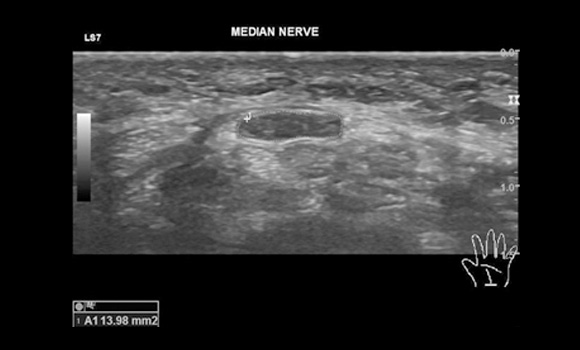

초음파 검사

신경의 부종을 영상을 통해 확인합니다